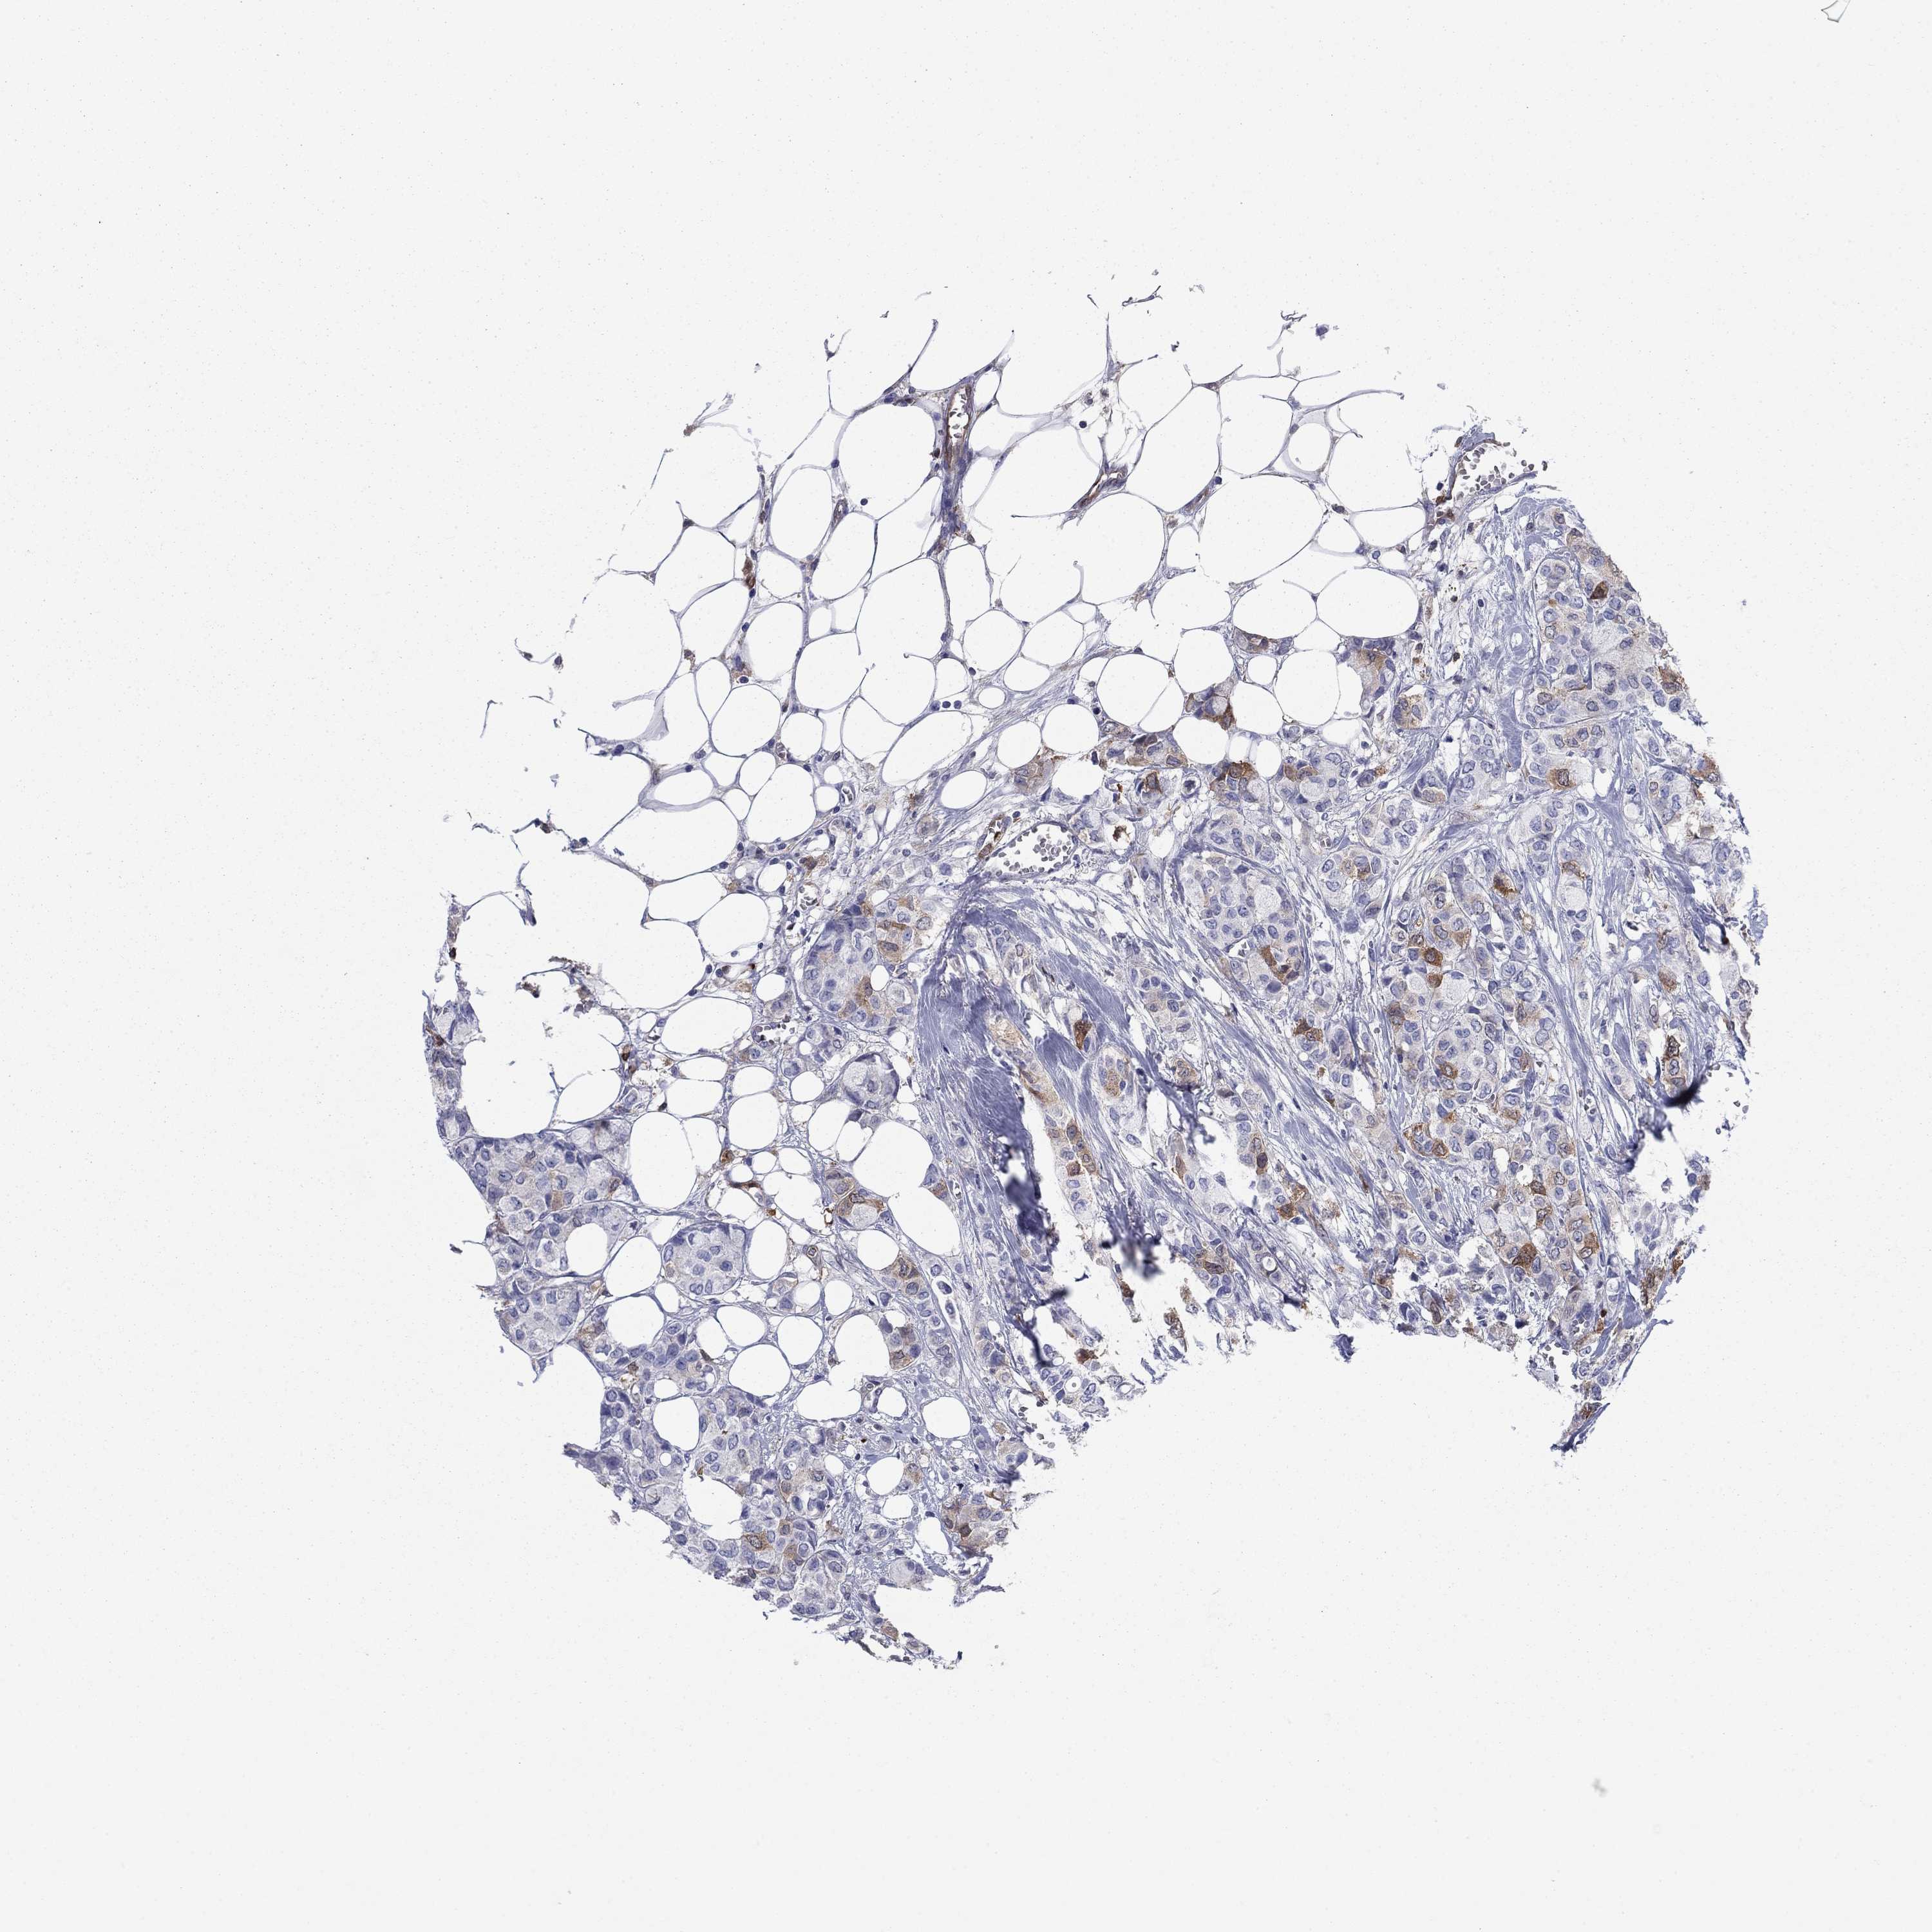

BRCA TCGA BRCA VALIDATION PROTEIN EXPRESSION

ANTIBODIES

AND

VALIDATION